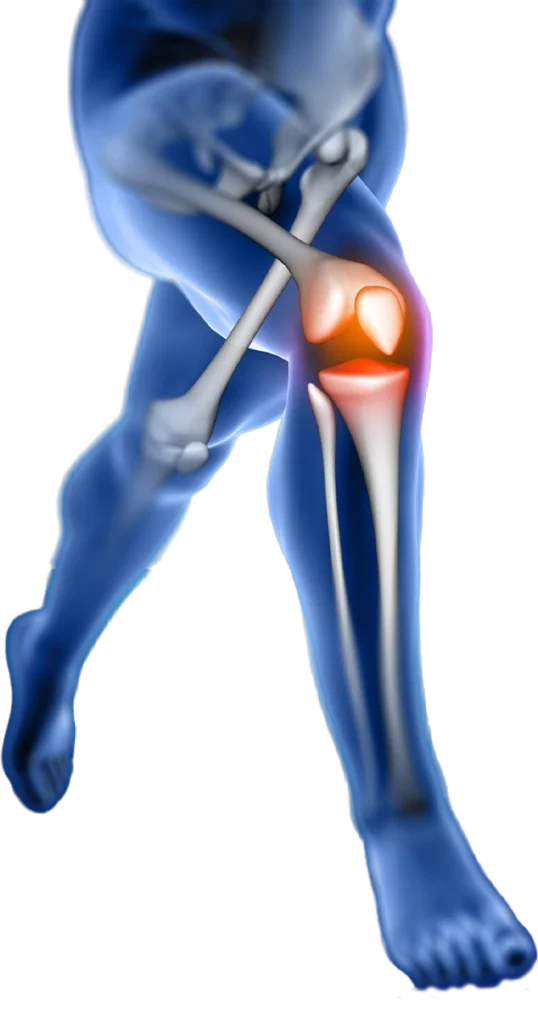

Lesões nos meniscos, que são estruturas em meia lua localizadas dentro das articulações do joelho. Elas são frequentemente causadas por movimentos de torção do joelho enquanto está carregando peso, como ocorre durante atividades esportivas. As lesões meniscais podem causar dor, inchaço ou travamento dos movimentos.

As reconstruções ligamentares são procedimentos cirúrgicos utilizados para reparar ou reconstruir os ligamentos do joelho lesionados, como o ligamento cruzado anterior (LCA), cruzado posterior (LCP) e lesões multiligamentares. Esses procedimentos geralmente envolvem a substituição do ligamento danificado por enxertos de tecido autólogo ou sintético, restaurando a estabilidade e função da articulação do joelho.